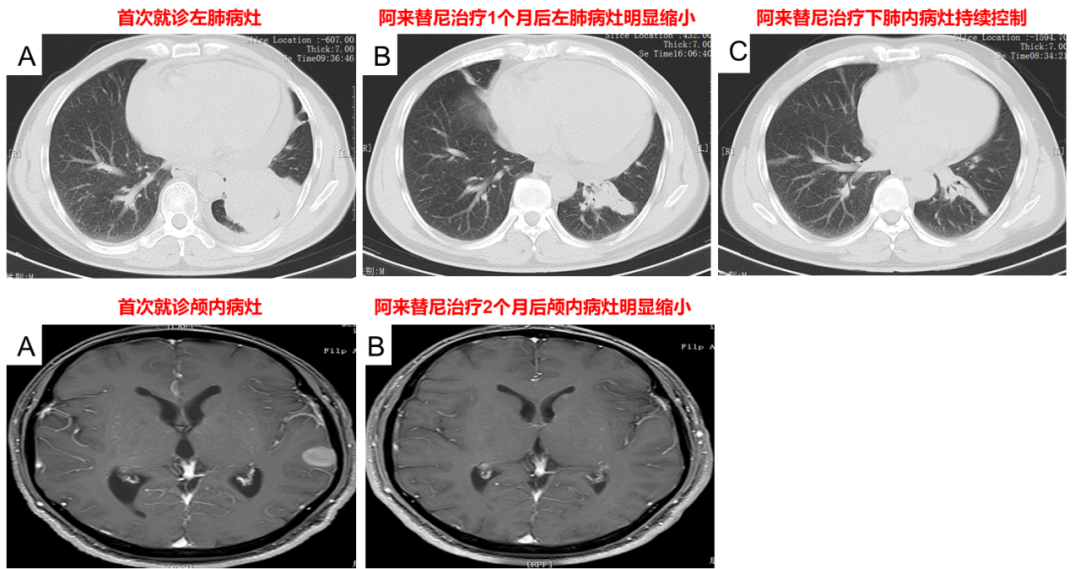

治疗经过(2022-5-9):口服恩沙替尼12d后转院就诊,因医保原因于2022-5-21更换为阿来替尼继续治疗,未见明显不适。1月后复查肺部、颅内病灶明显缩小,疗效评价PR,后多次复查评估肿瘤稳定。

图2. 阿来替尼治疗后复查肺部及颅内病灶明显缩小